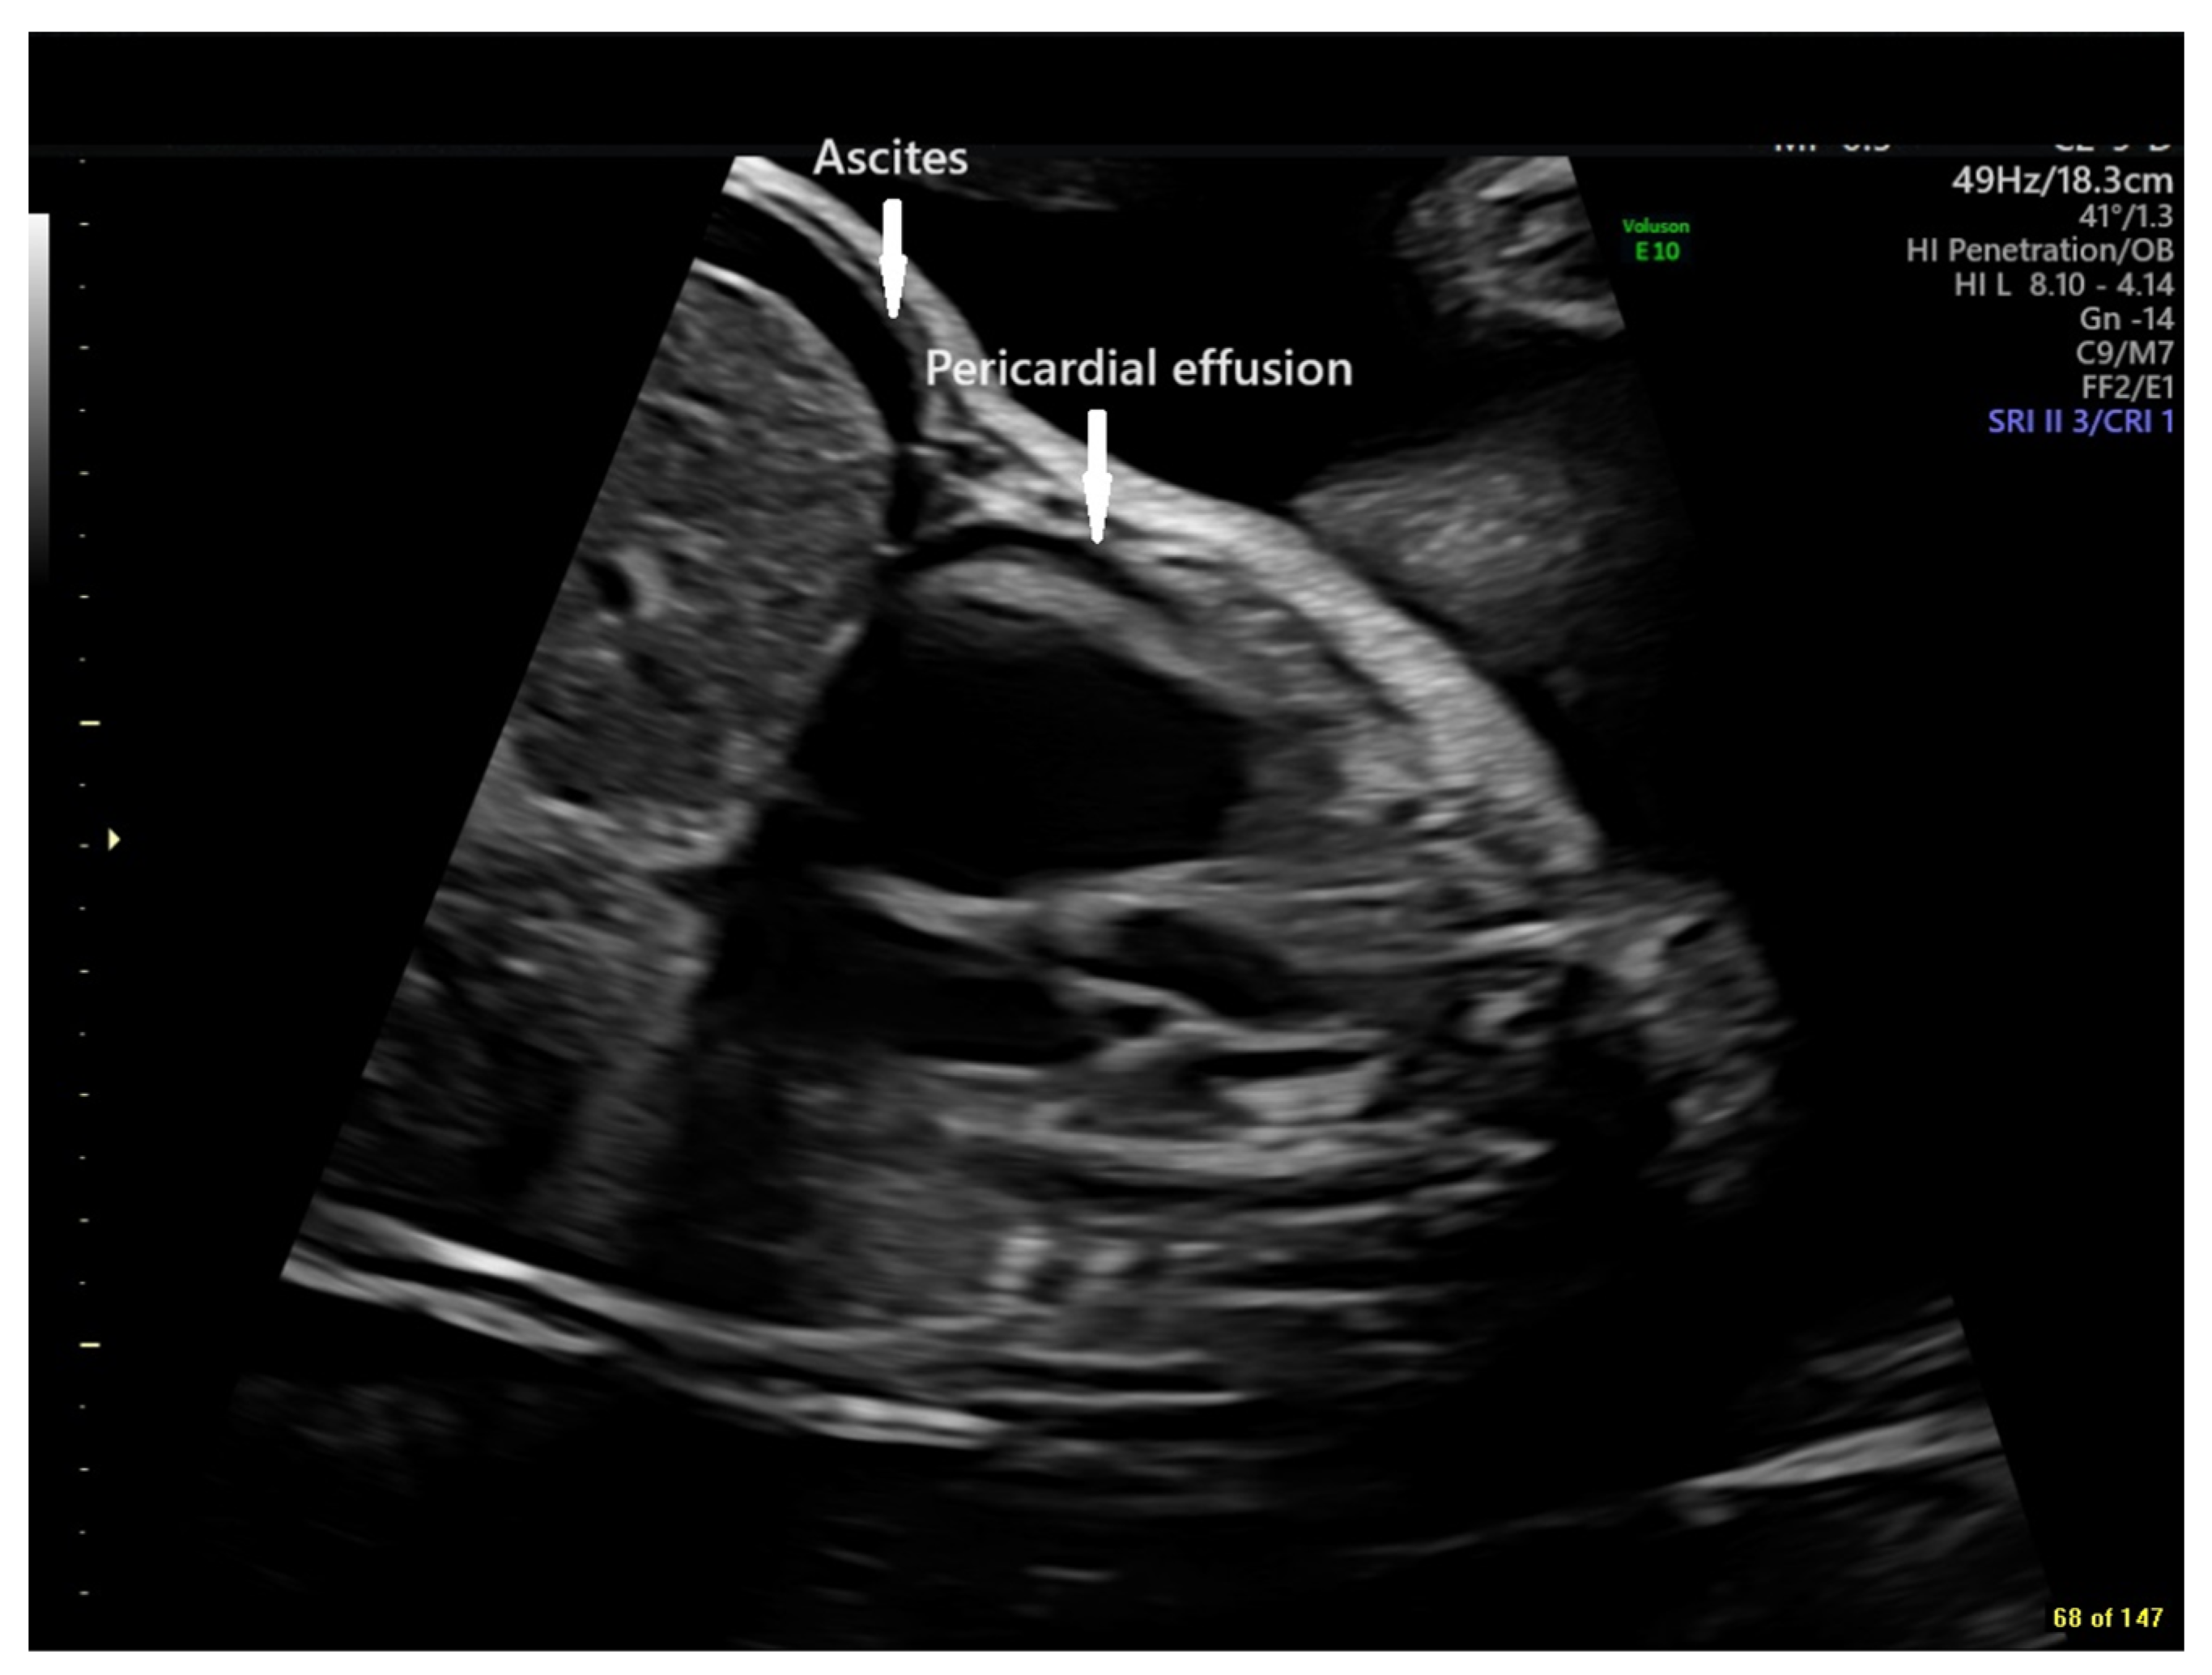

To address the evolving fetal decompensation in the setting of continued intermittent tachycardia and circular shunt physiology, flecainide was increased to 400 mg divided three times daily. After consultation with the fetal team at The Hospital for Sick Children in Toronto and a discussion of risks and benefits with the family, we agreed to start a trial of indomethacin 100 mg twice daily at 31 1/7 to attempt fetal ductal constriction. On this regimen, the fetal tachycardia was well controlled, and the fetus had evidence of ductal constriction by imaging (diameter Z score −3.4) and Doppler (peak systolic velocity 2.5 m/s; peak diastolic velocity 60 cm/s) by 31 6/7 weeks gestation with associated decrease in CT ratio, restoration of normal right ventricular systolic performance, and resolution of hydrops fetalis. Due to concerns that the ductal diameter had halved in 5 days, indomethacin was held for 48 h and restarted for only 48 h before being discontinued entirely at 32 3/7 weeks, at which time the ductus was difficult to resolve, with best estimates of size in images supplemented by color flow mapping at 2 mm (Z score −6.7) (Figure 4). There was antegrade flow of normal velocity at the pulmonary valve, mild pulmonary valve insufficiency, normal biventricular systolic performance, and no evidence of hydrops fetalis. Tricuspid regurgitation velocity remained low (2.2 m/s), and ensuing discussions with the family regarding postnatal management focused on plans for postnatal univentricular palliation.

Figure 4. Echocardiographic sagittal still frame image of the fetal thorax with color flow mapping demonstrating retrograde flow in a diminutive ductus arteriosus (arrow). RA = Right Atrium, AAo = Ascending Aorta, LA = Left Atrium, DAo = Descending Aorta (GE Voluson E10 Imaging System).